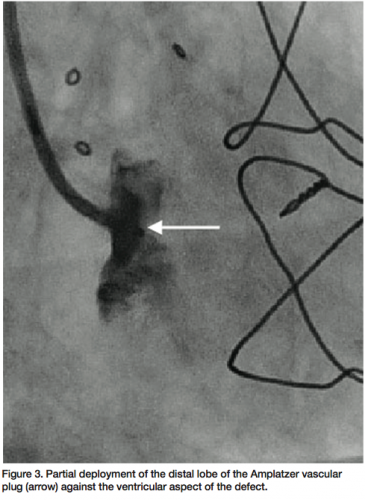

Glidewire was exchanged for an Amplatz stiff wire (Cook Medical) and a 6 French 90 cm Pinnacle sheath (Terumo Medical) advanced over the Amplatz stiff wire through the paravalvular defect into the left ventricle (Figure 2). The stiff wire was removed and a 10 mm Amplatzer vascular plug II (AGA Medical) advanced through the sheath. The distal lobe of the device was deployed on the ventricular side and withdrawn to pull against the ventricular aspect of the

defect (Figure 3). The two proximal lobes of the device were then packed against the aortic side of the defect and with adequate positioning confirmed, the delivery system disengaged and final angiographic (Figure 4) and transesophageal images obtained, demonstrating no significant aortic insufficiency (Figure 5). All catheters and sheaths were removed, with hemostasis achieved using a vascular closure device. The patient was discharged home the following day without any complications.